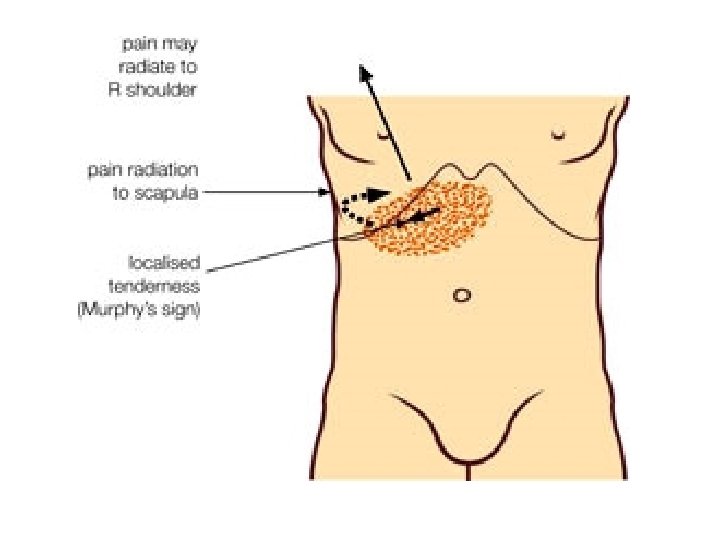

• KLINIKA: - Shenja kryesore eshte dhimbja abdominale e forte qe lokalizohet me veshtiresi nga i semuri. - Dhimbja: fillon ne regionin epigastrik, mund te perhapet edhe ne shpine ose ne shpatullen e djathte, por kryesisht perqendrohet ne kuadrantin superior dexter. - Eshte nje dhimbje me intensitet ne rritje. - Kjo dhimbje pasqyron tensionin dhe inflamacionin e mureve te kolecistes, si pasoje e obstruksionit kalkuloz te duktusit cistik.

• EKZAMINIMI FIZIK: - Abdomeni dolent ne palpim kryesisht ne kuadrantin superior dexter (hypokondrin dexter) - Rezistence=mbrojtje muskulare=defans (+) qe tregon per inflamacion te theksuar te kolecistes.